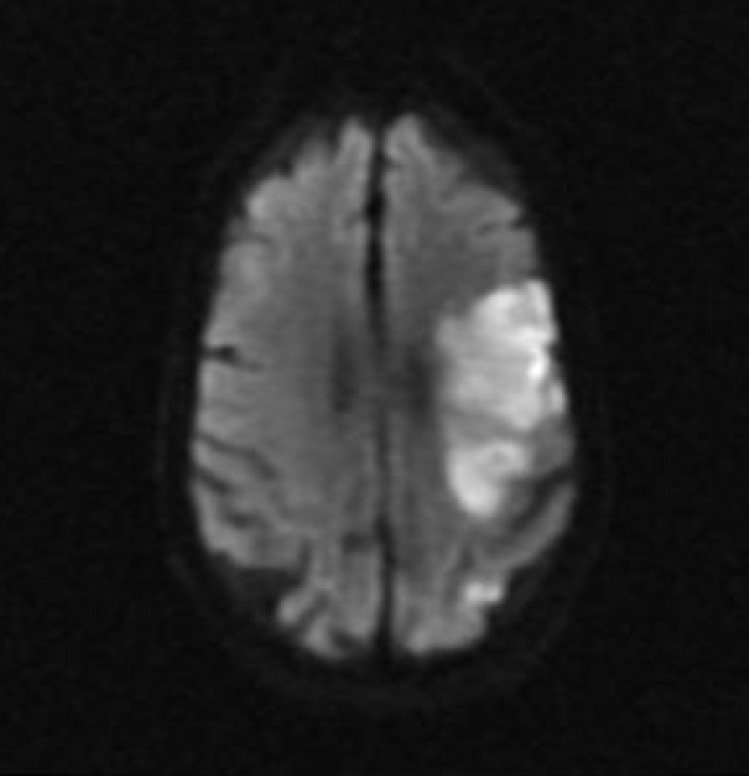

1. What do the different colours in this Diffusion Weighted image represent?

BRIGHT REGIONS:

- there is decreased water diffusion

- the Diffusion Weighted Image signal is high

- this is where the stroke will be found

DARK REGIONS:

- there is increased water diffusion

- the Diffusion Weighted Image signal is low